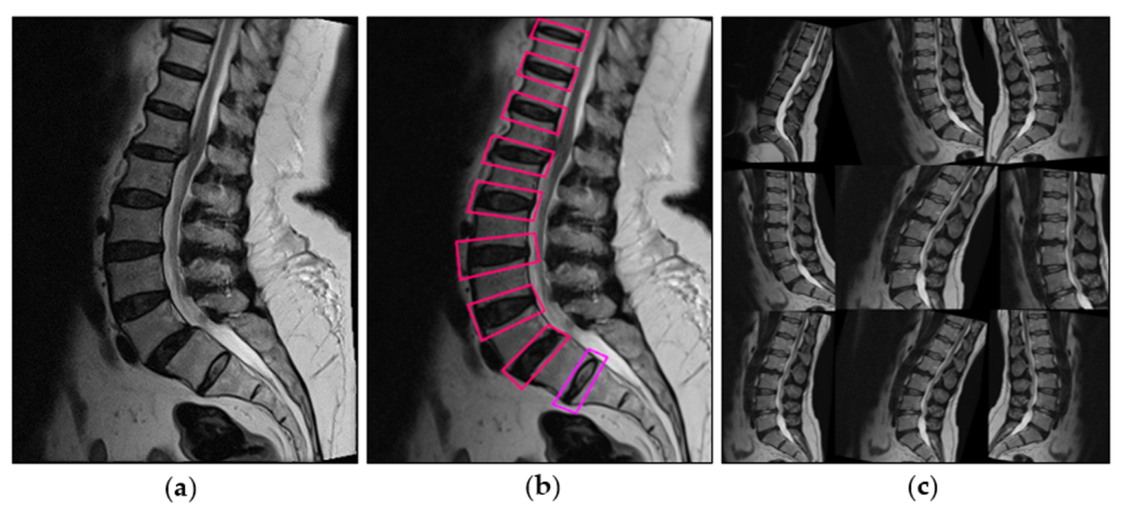

2.3. Image Preprocessing